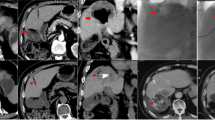

The DEI data derived from the 80 kVp and Sn150 kVp images and subjected to the 0.06 DEI threshold confirms that the imaging identifies tubes that contain iodine, whether alone or in combination with bismuth beads (Fig. 8). The HU map with the 20 HU threshold to exclude the agarose identified both iodine and bismuth within the tubes. The combination of the two maps (DEI map to identify iodine and HU to identify any radioabsorber) demonstrates that bismuth alone could be distinguished from iodine alone or the combination of iodine and bismuth.

Dual energy CT post-processing workflow and outcome for bismuth, iodine and mixture agarose phantoms. Row 1: Original 80 kVp and Sn150 kVp energy reconstructions. Row 2: A dual energy index (DEI) image is calculated from the two scans. Row 3: DEI values greater than 0.06 are superimposed on the original DEI image as a red color map. (left image). Image intensity values above 20 HU in the Sn150 kVp image are superimposed on the original image as a green color map (right image). Row 4: Combined DEI and HU color maps as blended color maps superimposed on the Sn150 kVp image. High HU above the threshold (green) occurs for both iodine and bismuth, however, the increase in DEI (red) only occurs for iodine. Therefore, bismuth alone can be differentiated from either iodine alone or a bismuth/iodine mixture, due to the absence of red.

DECT imaging may be used for material classification by exploiting the differences in X-ray absorption of iodine and bismuth from high radiographic density. This model could also be imposed in the clinical setting of liver tumor embolization. A DEI threshold of 0.06 distinguished iodine from the background and from bismuth beads alone. However, there was an overlap in DEI values for the higher concentrations of bismuth beads and the lower concentrations of iodine. Therefore, the DEI as a single image feature could be used to identify if iodine was present, either alone or in combination with bismuth beads. The model dictates that densities (HU) above background must be either iodine or bismuth, while any tube with a DEI below the threshold that does not contain iodine and must be bismuth beads. For embolization, the only density would be iodine or bismuth beads. Refining and optimizing the synthesis process to increase the selection of only the bead populations with higher radiographic density could lead to an increase in the signal to noise ratio in CT scanning and material decomposition. The DEI could be used to define and follow the washout of iodine contrast after embolization. Post-embolization residual tumor enhancement may be hard to distinguish from high attenuation iodine beads, without a subtraction image in conventional CT. Bismuth beads would not present this problem16. These novel bismuth beads have the potential to improve image-guided local drug delivery in patients with liver cancer by directly identifying either non-targeted delivery or undertreated tumor. The ability to choose from two bead formulations to load drugs opens the door to dual drug delivery and “dual drug dose tracking”. Two beads could be loaded with doxorubicin and a second agent, such as an immunomodulator. Two drugs could be selected and targeted with a mechanistic rationale that factors in the tumor microenvironment or molecular data. For example, doxorubicin intercalates in the nucleus and is more active for cell-cycle-specific regions of high mitosis, which may be reflected by high metabolic activity on FDG PET. Necrosis-targeting agents could be loaded and localized by injection into imaged regions of necrosis or high interstitial pressure, such as regions with restricted diffusion on MRI. Anti-vascular agents loaded on an image-able bead could be targeted to areas of high enhancement or vascular density, also easily localized on imaging. Fused imaging on top of procedural CBCT also allows exquisite mechanistic targeting, in such a paradigm17. Combining iodine-based and a bismuth-based beads loaded with different chemotherapy or immunotherapy drugs, could potentially enable dual drug delivery for a more rational, fusion image guided therapy grounded in mechanistic molecular reasoning. Such a paradigm could move image guided therapies into a new era after the field has delivered the same anthracycline for over four decades18.